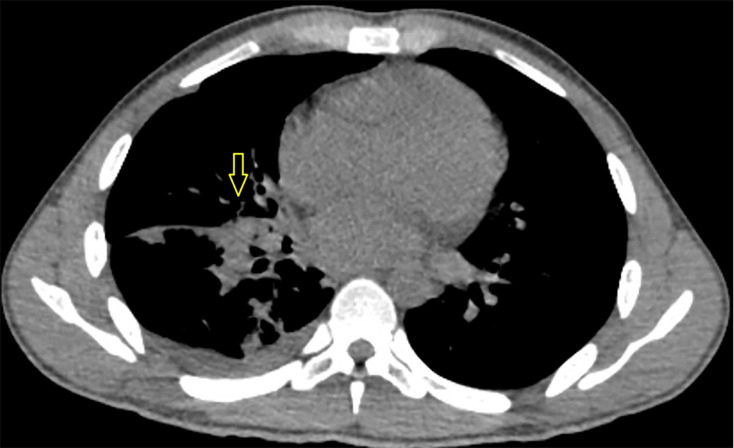

Introduction. Coccidioidomycosis, or Valley fever, is a fungal disease caused by Coccidioides species, prevalent in parts of the southwestern United States. It usually results from inhaling spores from soil and is a common cause of pneumonia in these regions. Case Presentation. We present a unique case of coccidioidomycosis in an immunodeficient male patient secondary to human immunodeficiency virus infection with poor adherence to anti-retroviral treatment. After presenting with non-specific symptoms and pre-syncope, he was initially diagnosed with pneumonia based on chest X-ray findings, but his symptoms failed to improve with antibiotics. He was treated for presumed pulmonary histoplasmosis following a positive histoplasma urine antigen test. However, the patient worsened clinically. Following a computed tomography scan demonstrating a large necrotic lung consolidation, fungal stain and culture of tissue biopsied through endobronchial ultrasound confirmed coccidioidomycosis. The patient received 2 weeks of liposomal amphotericin with clinical improvement before discharge with itraconazole. Conclusion. The histoplasma antigen test can be falsely positive due to cross-reaction with other fungal infections like blastomycosis, paracoccidioidomycosis or talaromycosis, and less frequently, coccidioidomycosis or aspergillosis. Diagnosis of coccidioidomycosis requires a high index of suspicion outside the expected geographic distribution in the appropriate clinical setting. Our case highlights the risk of false-positive antigen test results and the importance of invasive diagnostics, including bronchoscopy to obtain fungal cultures, if the diagnosis remains uncertain.